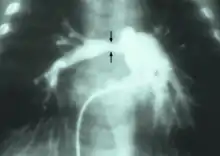

Stenosis of pulmonary artery

Stenosis of the right pulmonary artery in a patient which was due to a case of congenital rubella.